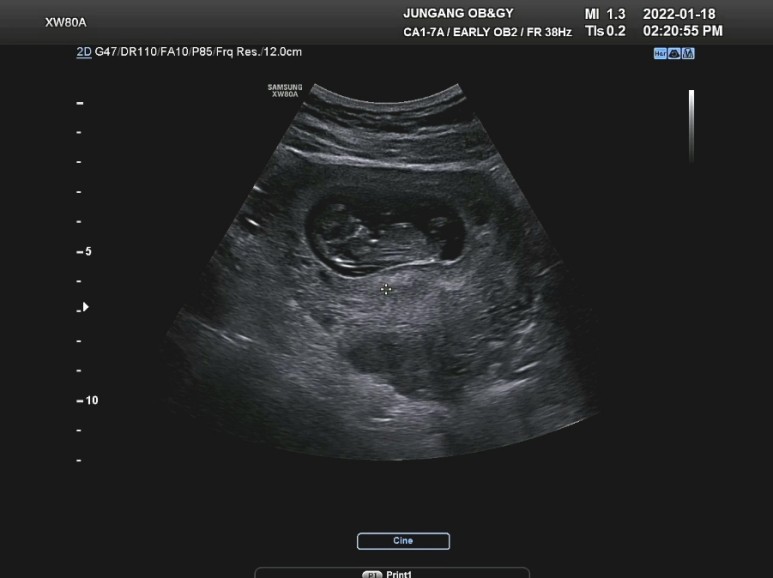

10주차를 기점으로 전에 없던 배의 통증도 눈에 띄고 예민해지고 불안해져서 인근 산부인과도 한 번 다녀왔다.

다행히도 많이자라서 열심히 놀고있는 다복이를 보니 안심이되었어